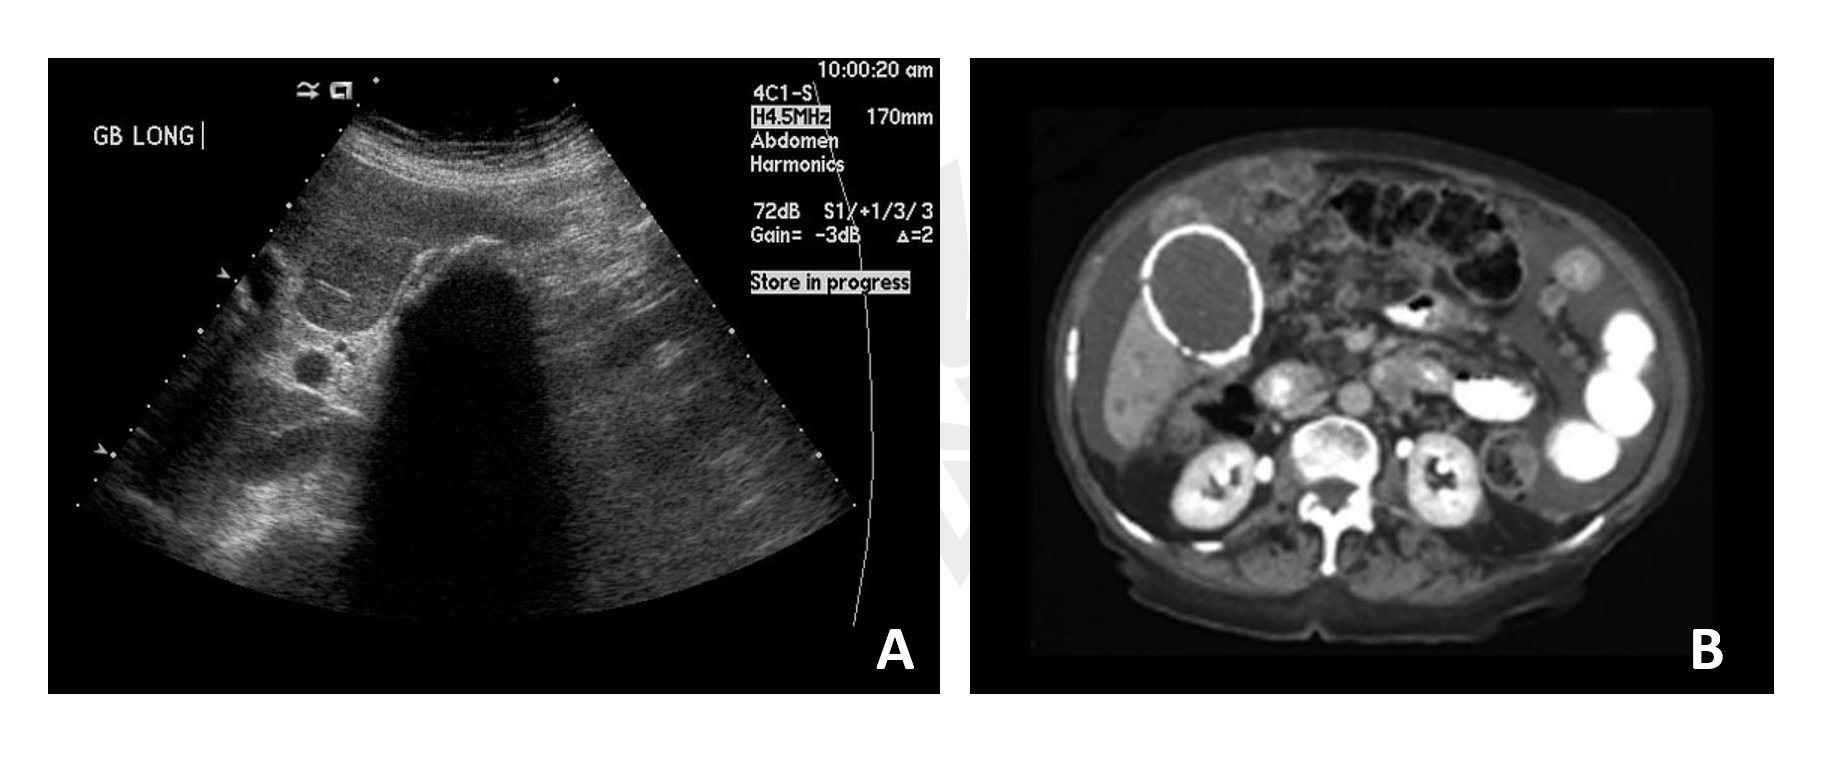

Ultrassonografia de abdome, Tomografias e até mesmo radiografias podem denotar a presença de uma vesícula em porcelana.

Fonte: radiopaedia.org Note que no Ultrassom (figura A), a calcificação da parede não permite a passagem do som, formando intensa sombra acústica – vista como um “vazio” no exame. Já na tomografia de abdome (figura B), podemos ver um halo esbranquiçado na topografia da vesícula, denotando a calcificação da parede.